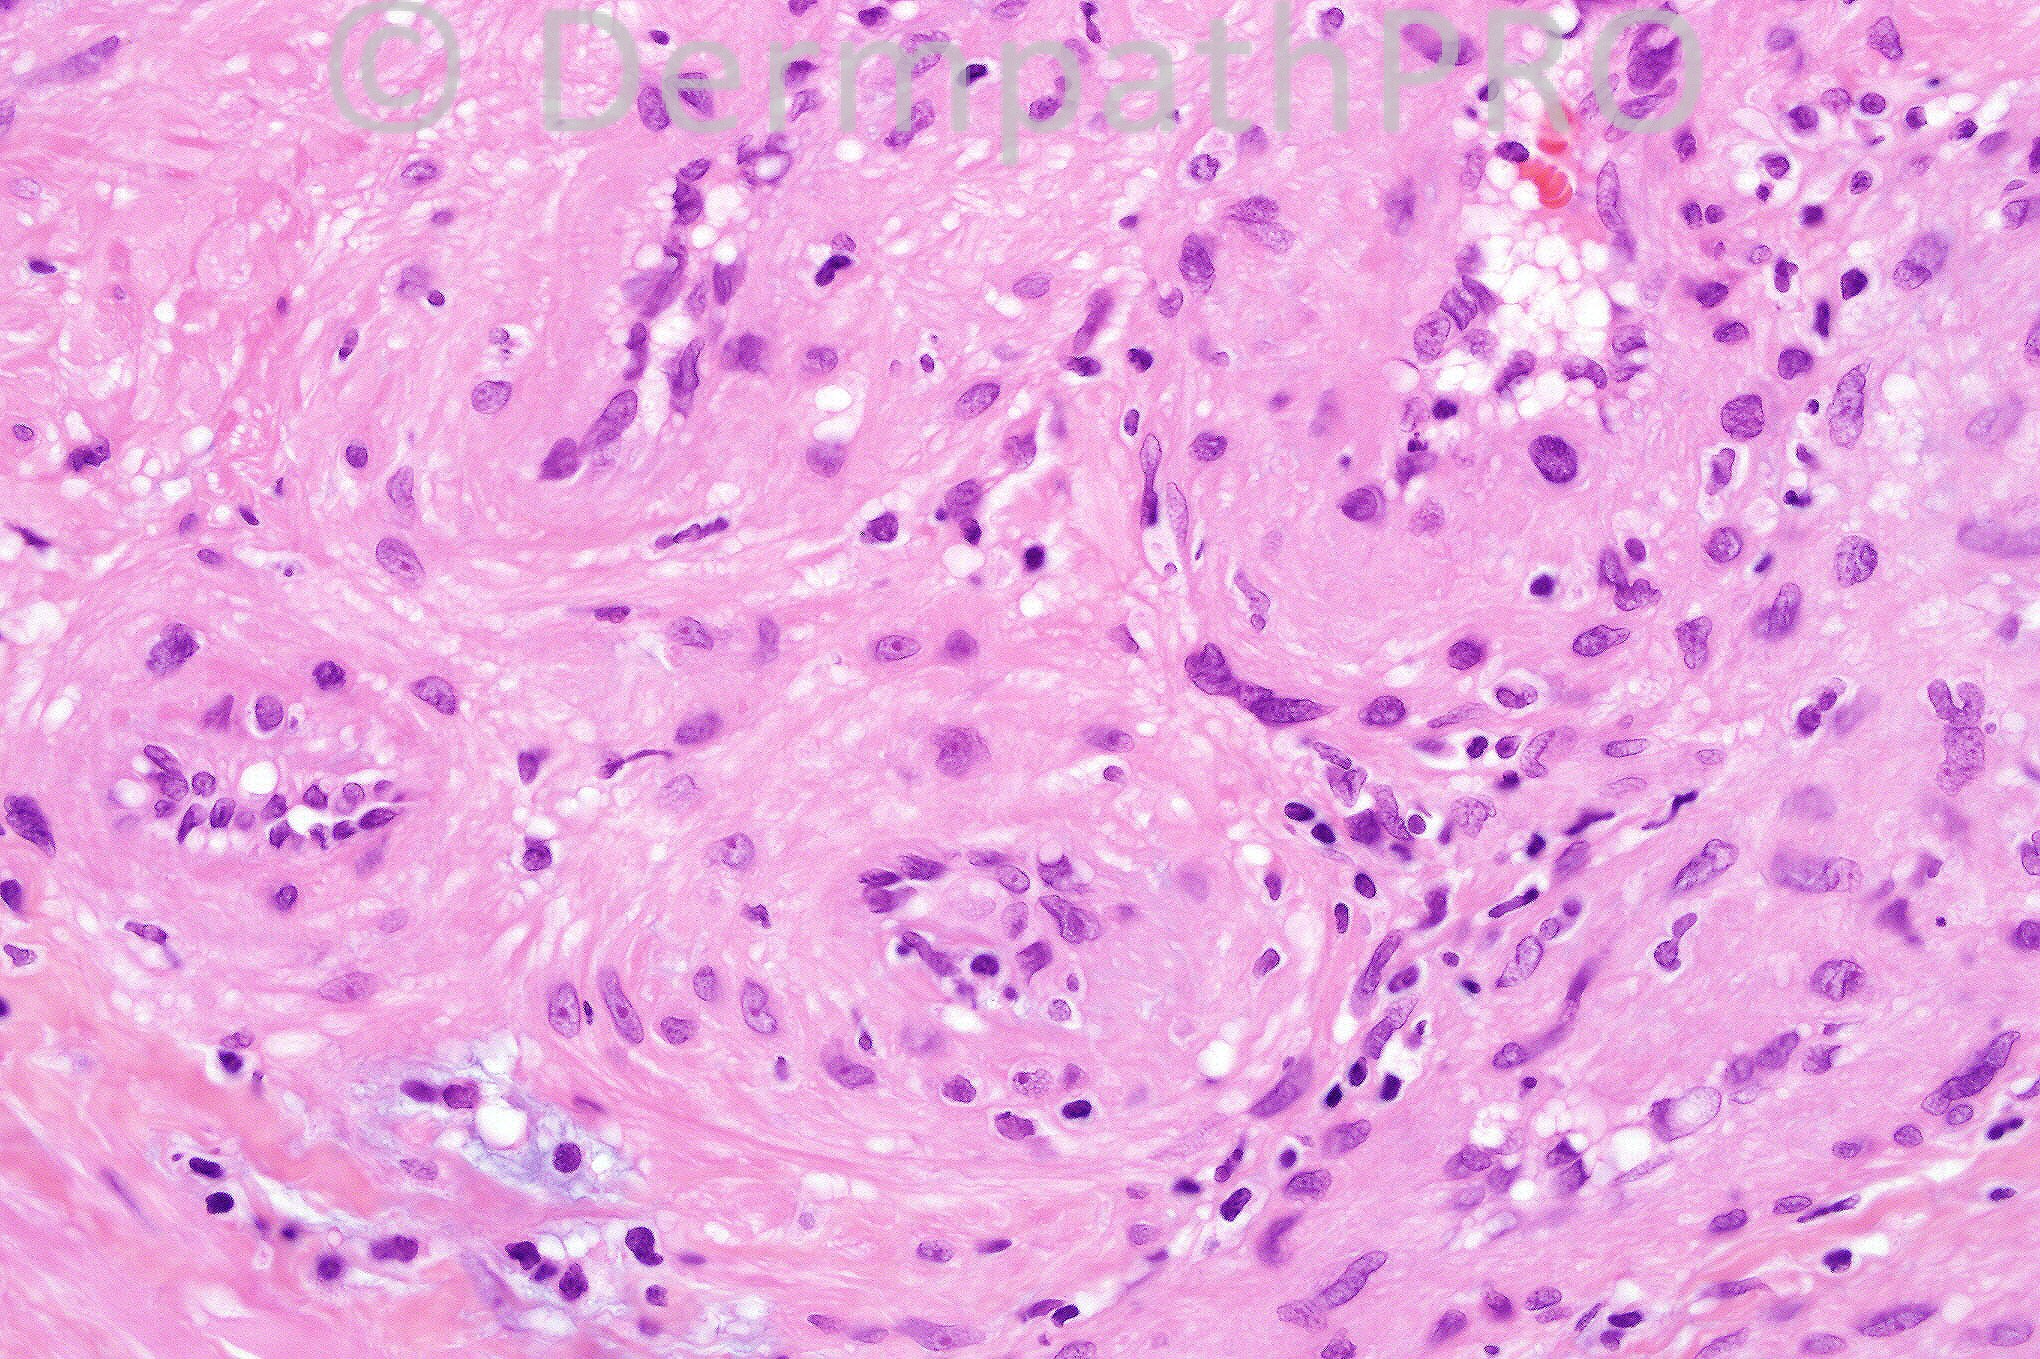

Female 47 years with a painful nodule on the trunk.